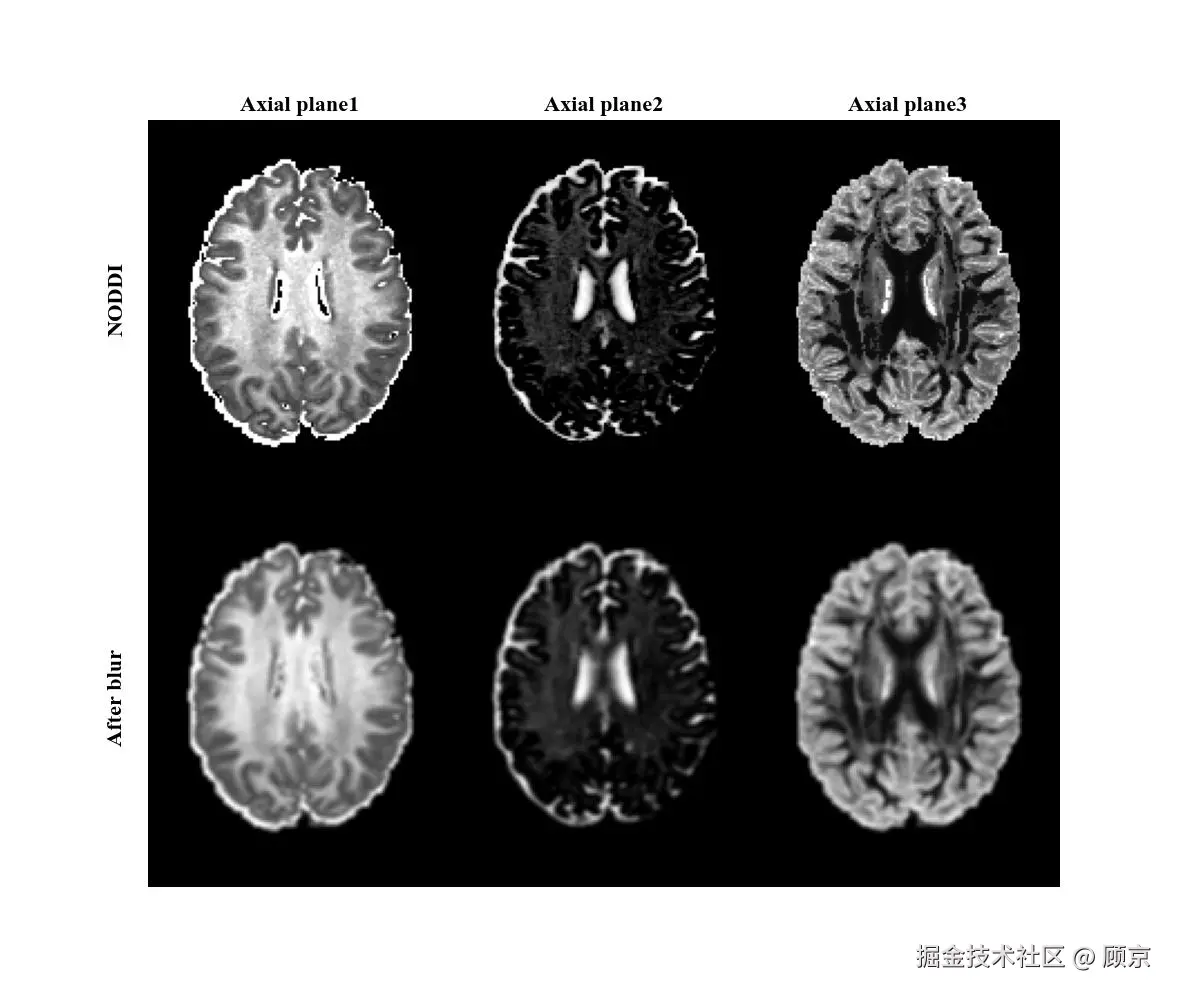

加噪方式比较好理解,实现也简单,生成一堆高斯噪声往上丢就可,如图1所示。

图1 添加高斯噪声